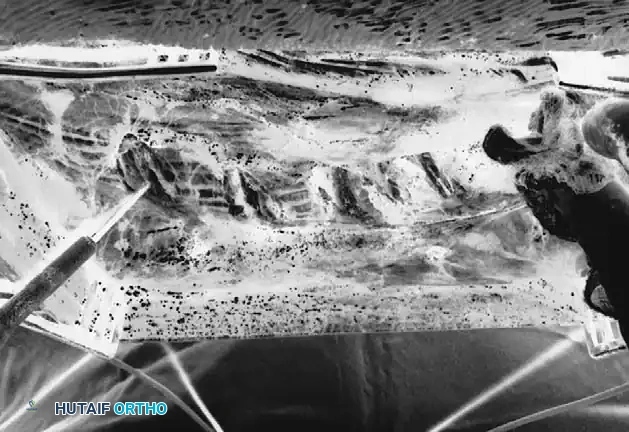

Rib Identification and Periosteal Stripping

- Palpation and Marking: Once the fascia is retracted laterally, palpate the ribs starting precisely at the apex of the deformity. Mark the apical rib with electrocautery. Symmetrical resection is planned, working distally and proximally one rib at a time. Usually, between four and six ribs are outlined for resection.

- Lateral Periosteal Stripping: Use a periosteal elevator to strip the periosteum off the superficial surface of the rib out to the lateral edge.

- Inferior Edge Stripping: Once the superficial periosteum is stripped to the side, use the elevator to carefully strip the periosteum and intercostal muscle attachments around the inferior edge of the rib.

- Anterior Stripping (The Danger Zone): With a curved Cobb elevator, strip the periosteum from the anterior (deep) aspect of the rib in a medial to lateral direction. This is the step where the pleura is most vulnerable and most likely to be entered. Keep the instrument firmly applied to the bone.

- Retractor Placement: Once the anterior aspect of the rib has been safely stripped, pass a Doyen rib retractor circumferentially from medial to lateral around the exposed rib to protect the underlying pleura.

- Medial Cut: Identify the most medial attachment of the rib to the transverse process. Pass a heavy rib cutter around the rib, pushing it as far medially as possible. Secure the rib segment with a towel clip or Kocher clamp. This prevents the sharp end of the rib from plunging downward through the pleura the moment it is cut. Cut the rib medially, keeping the blades of the cutter as parallel to the floor as possible to avoid leaving a sharp, downward-pointing spike.

- Lateral Cut and Resection Limits: Make the lateral cut. For a standard rib resection in a patient with a 55-degree right thoracic curve, approximately 2 cm of rib should be cut initially at the apex.

- Sequential Resection: Cut the additional outlined ribs in an identical fashion, moving proximally and distally from the apex, progressively removing shorter segments of rib to create a smooth contour.